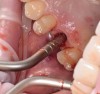

After the surgical stent was tried in and verified (Figure 5), a 5-mm tissue punch was introduced through the surgical stent to remove a core of soft tissue where the implant would be placed. Osteotomy drills matching the implant system to be used were introduced through the surgical stent and taken to the final diameter. The stent limited the depth to 2-mm short of the sinus floor. The stent was removed, the final drill was reinserted into the osteotomy, and a periapical radiograph was taken to verify the depth and orientation to the sinus floor (Figure 6). Next, a 5-mm wide, cupped-end sinus osteotome was introduced into the osteotomy, and another periapical radiograph was taken to check the depth of the osteotomy in relation to the sinus floor. Using a surgical mallet, the osteotome was advanced an additional 4 mm with gentle tapping to elevate the sinus floor atraumatically (Figure 7). A blunt instrument was used to verify the integrity of the sinus membrane and confirm that perforation had not occurred during the sinus lift. Following verification of sinus integrity, the previously created A-PRF+ plugs (Figure 8) were removed from the PRF box and individually placed into the osteotomy (Figure 9). The 5-mm osteotome was used to efficiently press the plug into the osteotomy, filling the space created between the sinus floor and the sinus membrane (Figure 10). The 5.2 x 10 mm implant with fixture mount attached was picked up with the handpiece driver on a surgical handpiece (Figure 11). The implant was inserted with the handpiece using 20 rpms until an insertion torque of 40 Ncm was reached. Final seating of the implant was accomplished with a torque wrench, which was used until the implant was positioned at the correct depth in relation to the site's crestal bone and the cementoenamel junction of the adjacent teeth (Figure 12). The fixture mount was removed, a cover screw was placed into the implant, and a periapical radiograph was taken to verify placement (Figure 13). Because the A-PRF+ is radiolucent when initially placed, its position cannot be ascertained radiographically at the time of surgery. The patient was scheduled for a 1-week postoperative check, at which time the cover screw was visible with slight irritation of the gingiva around its periphery. At the 3-week postoperative examination, the cover screw remained exposed, but the peripheral gingival inflammation was absent and the tissue appeared normal in color and tone.